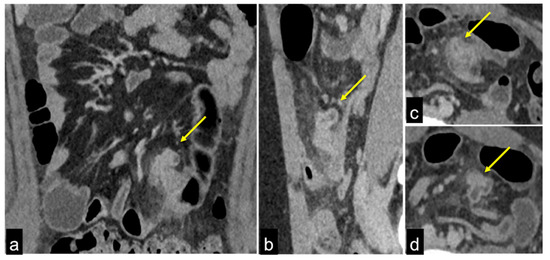

| Haemobilia (Figure 32) | Melaena, haematemesis, biliary colic, jaundice, or massive bleeding in a patient with a history of blunt or iatrogenic abdominal trauma. | Presence of blood in the gallbladder and biliary tree. |